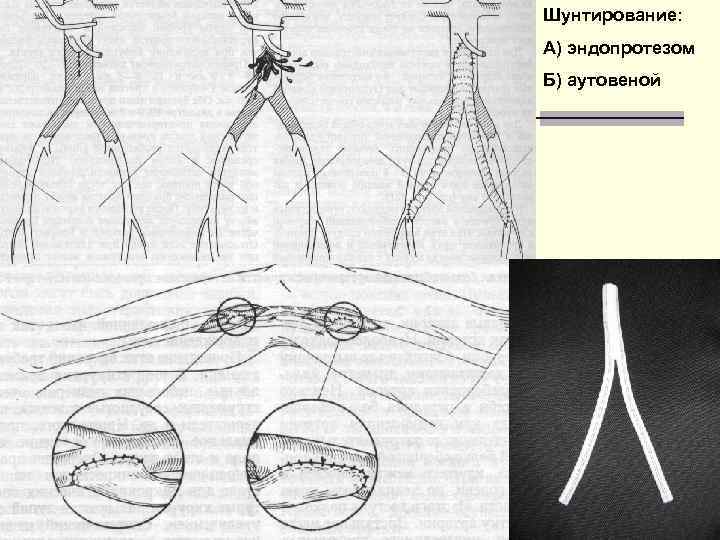

Лечение n При остромбозе показано обследование больного и подготовка его к последующей реконструктивной операции на сосудах. n В наиболее тяжелых случаях и в остром периоде производят тромбинтимэктомию, протезирование сосуда или обходное шунтирование. 29

Шунтирование: А) эндопротезом Б) аутовеной 31

Лечение n Оперативное лечение - при наличии ограниченной окклюзиии на уровне бифуркации аорты, подвздошных артерий, а также венечных артерий сердца. n Использует реконстуктивные сосудистые операции трех видов – тромбинтимэктомию, n резекцию сосуда последующим протезированием n обходное шунтирование. n 62